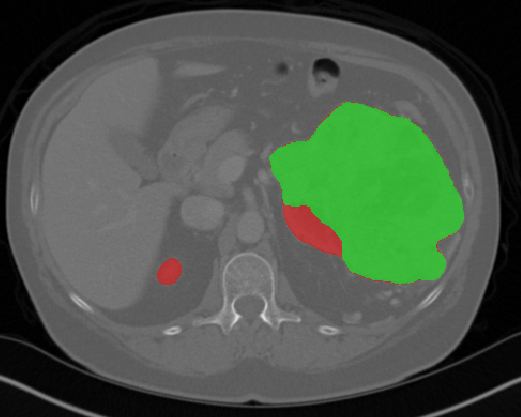

Edge-Aware 3D Image Segmentation Networks

[91]: Automated segmentation of kidneys and kidney tumors is an important step in quantifying the tumor’s morphometrical details to monitor the progression of the disease and accurately compare decisions regarding the kidney tumor treatment. Manual delineation techniques are often tedious, error-prone and require expert knowledge for creating unambiguous representation of kidneys and kidney tumors segmentation. We propose a 3D end-to-end edge-aware FCN for reliable kidney and kidney tumor semantic segmentation from arterial phase abdominal 3D CT scans. Our segmentation network consists of an encoder-decoder architecture that specifically accounts for organ and tumor semantics. We evaluate our model on the 2019 MICCAI KiTS Kidney Tumor Segmentation Challenge dataset. -

Kidney and Kidney Tumor Segmentation

Kidney cancer accounted for nearly 175,000 deaths worldwide in 2018 [13], and it is projected that 14,770 deaths will occur due to the disease in 2019 in the US [111]. Current kidney tumor treatment planning includes Radical Nephrectomy (RN) and Partial Nephrectomy (PN). In RN, both the tumor and the affected kidney are removed whereas in PN the tumor is removed but kidneys are saved [116]. Although RNs were historically prevalent as a standard treatment procedure for kidney tumors, new capabilities for earlier detection of the tumors as well as advancements in surgery has made PNs a viable treatment approach [53].

Traditionally, various techniques such as deformable models [86], GrabCuts, region growing and atlas-based methods have been applied to the problem of kidney segmentation. In recent years, researchers have attempted to leverage the power of deep learning and CNNs to build segmentation frameworks that are more automated and less dependant on incorporation of prior shape statistics. Thong et al. [119] proposed a 2D patch-based approach for kidney segmentation in contrast-enhanced CT scans by leveraging a modified ConvNet.

Jackson et al. [62] developed a framework for detection and segmentation and of kidneys in non-contrast CT images by utilizing a 3D U-Net. Yang et al. [128] proposed a method for kidney and renal tumor segmentation in CT angiography images by a modified residual FCN that is equipped with a pyramid pooling module. Furthermore, Yin et al. [130] employed a cascaded approach for segmentation of kidneys with renal cell carcinoma by training a CNN that predicts a bounding box around the kidney and a subsequent CNN that segments the kidneys. Recently, Xia et al. [126] proposed a two-stage approach for the segmentation of kidney and space-occupying lesion areas by using SCNN and ResNet for image retrieval and SIFT-flow and MRF for smoothing and pixel matching.